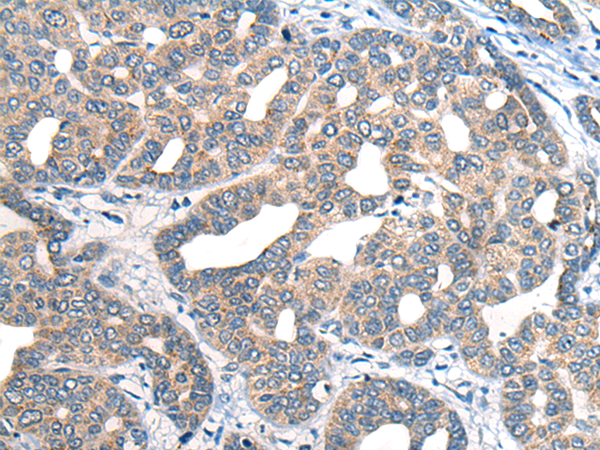

分类: 科研抗体货号: P13149别名: HB1; HB2; HH1; IVF; VF1; HBBD; ICCD; LQT3; SSS1; CDCD2; CMD1E; CMPD2; PFHB1; Nav1.5应用: IHC反应种属: Human, Mouse, Rat